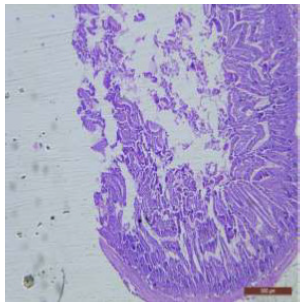

In fluoridated rats damaged and broken villi, focal intervillous haemorrhages and ulceration was present (Figure 12). There was shortening and flattening of some of the villi (Figure 13), distorted crypts, large swollen goblet cells lined by columnar epithelium with wide spaces were present (Figure 14). Distortion of different layers of mucosa with the loss of villous architecture and shedding of surface epithelium was seen in the jejunum of fluoridated rats (Figure 15). The villus architecture was notably disturbed, with a marked loss of crypts. Furthermore, there was a noticeable decrease in the number of goblet cells (Figure 16). The villi appeared scattered and fragmented, indicating a disruption in their typical architecture. Reduction in size of intestinal glands highlighted the detrimental impact of fluoride exposure on the intestinal morphology of rats (Figure 17).

Figure 12: T.S. of jejunum of rat treated with 600 mg NaF/kg b.w./day for 40 days showing ulceration, focal intravillous hemorrhages and broken villi (↑). H&E × 100.

The ileal mucosa of control rat was built up of numerous folds forming the villi, through which connective tissue of the lamina propria containing tubular glands i.e., crypts of Leiberkühn were present (Figure 18). The epithelial lining of the villi was composed of Paneth cells and intestinal glands (Figure 19). In fluorotic rats, there were abnormal shaped, damaged and broken villi with bulbous tips. Lymphatic dilation and haemorrhaged in lamina propria were also seen (Figure 20). In the ileal mucosa, prominent inflammation, distortion of crypts with shredded cells inside the crypts were visible (Figure 21). Swollen and necrotic crypts were present (Figure 22). The ileal tissue showed disruptions in the normal mucosal architecture with signs of villous atrophy and cell infiltration (Figure 23). Lymphatic infiltration was prominent and numerous enlarged lymph nodules appeared in lamina propria of villi. There were ill-defined cell boundaries, vacuolated cytoplasm and pyknotic nuclei (Figure 24).

Figure 13: T.S. of jejunum of rat treated with 600 mg NaF/kg b.w./day for 40 days showing distortion, shortening and flattening of villi (↑). H&E × 100.

Figure 15: T.S. of jejunum of rat treated with 600 mg NaF/ kg b.w./day for 40 days showing atrophy of villi and distortion of different layers and destruction of surface epithelium (↑). H&E × 100.

Figure 16: T.S. of jejunum of rat treated with 600 mg NaF/ kg b.w./day for 40 days showing disruption of villi (↑), reduction in number of goblet cells (↑) and crypt loss (↑). H&E × 100.